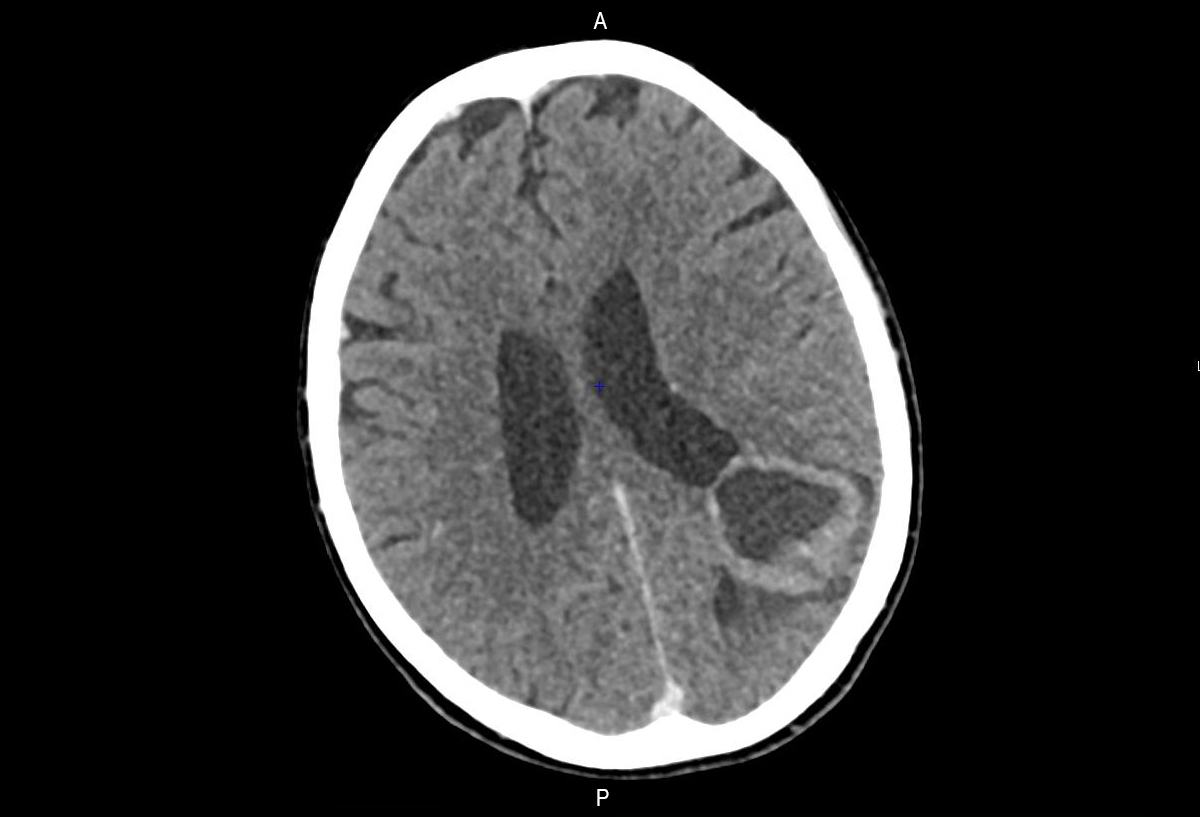

L’examen neurologique ne retrouve pas de déficit sensitif ni moteur, en dehors de la somnolence elle est consciente et orientée. Les nerfs crâniens sont intègres, les pupilles réactives et symétriques. Il n’y a pas de syndrome méningé. Elle marche lentement, mais sans ataxie. Les réflexes ostéotendineux sont retrouvés bilatéraux et symétriques, le réflexe cutanéo-plantaire est en flexion à gauche, en extension à droite.

Question 1 - Parmi les informations qui sont à votre disposition, celle(s) orientant vers une crise d’épilepsie plutôt que vers une syncope est/sont :

Ici c’est le déficit postcritique prolongé qui est l’élément le plus parlant.